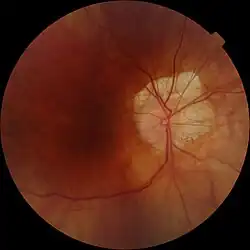

Creciente miópico

El creciente miópico, también llamado creciente temporal, cono miópico, creciente escleral y coloboma de Fuchs, es un término que se utiliza en oftalmología para designar un área con forma de semiluna, de color blanco, que se encuentra situada en la retina, próxima a la papila óptica en su zona temporal.[cita requerida]

Puede estar presente desde el momento del nacimiento aunque lo más frecuente es que se haga visible en la pubertad, cuando el ojo crece rápidamente, adelgazando la coroides y el epitelio pigmentario de la retina, dejando ver el color blanco de la esclera. Fue descrita por el médico austriaco Ernst Fuchs (1851-1930).

Cuando un oftalmólogo u óptico-optometrista realiza una exploración del ojo, es frecuente que use un dispositivo óptico que se llama oftalmoscopio para poder ver la retina (la capa más interna de la pared del ojo en la que se encuentran las células sensibles a la luz). Durante este examen puede descubrir una mancha de color blanquecino y forma de semiluna que esta próxima a una región de la retina que se llama papila. En la papila es donde se origina el nervio óptico. Esta mancha blaquecina se denomina creciente papilar y aparece muy frecuentemente en las personas con miopía avanzada, sin que su presencia indique la existencia de ningún tipo de complicación grave.

El creciente miópico corresponde a una parte de la esclera (la capa más externa que forma la pared del ojo) que no está cubierta por la coroides ni por el epitelio pigmentario de la retina.